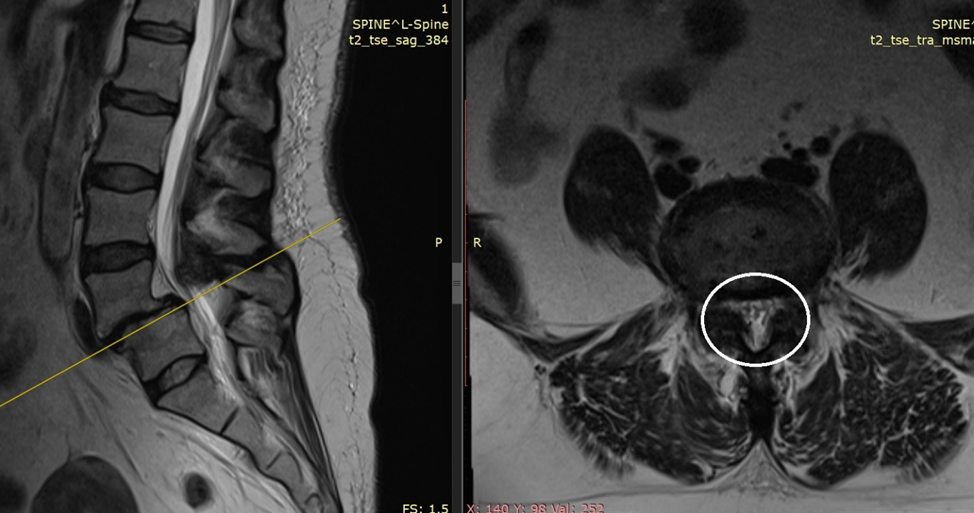

Нормальный размер позвоночнго канала - обведено белым кругом

Вот так должен выглядеть позвоночник, белым кругом обведена норма - когда отверстие позвоночного канала большое.